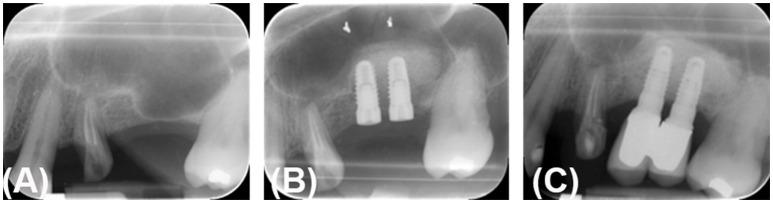

Sinus lift augmentation is a procedure required for the placement of a dental implant, whose success can be limited by the quantity or quality of available bone. To this purpose, the first aim of the current study was to evaluate the ability of autologous periosteum-derived micrografts and Poly(lactic-co-glycolic acid) (PLGA) supplemented with hydroxyl apatite (HA) to induce bone augmentation in the sinus lift procedure. Secondly, we compared the micrograft's behavior with respect to biomaterial alone, including Bio-Oss® and PLGA/HA, commercially named Alos. Sinus lift procedure was performed on 24 patients who required dental implants and who, according to the study design and procedure performed, were divided into three groups: group A (Alos + periosteum-derived micrografts); group B (Alos alone); and group C (Bio-Oss® alone). Briefly, in group A, a small piece of periosteum was collected from each patient and mechanically disaggregated by Rigenera® protocol using the Rigeneracons medical device. This protocol allowed for the obtainment of autologous micrografts, which in turn were used to soak the Alos scaffold. At 6 months after the sinus lift procedure and before the installation of dental implants, histological and radiographic evaluations in all three groups were performed. In group A, where sinus lift augmentation was performed using periosteum-derived micrografts and Alos, the bone regeneration was much faster than in the control groups where it was performed with Alos or Bio-Oss® alone (groups B and C, respectively). In addition, the radiographic evaluation in the patients of group A showed a radio-opacity after 4 months, while after 6 months, the prosthetic rehabilitation was improved and was maintained after 2 years post-surgery. In summary, we report on the efficacy of periosteum-derived micrografts and Alos to augment sinus lift in patients requiring dental implants. This efficacy is supported by an increased percentage of vital mineralized tisssue in the group treated with both periosteum-derived micrografts and Alos, with respect to the control group of Alos or Bio-Oss® alone, as confirmed by histological analysis and radiographic evaluations at 6 months from treatment.

上颌窦提升术是种植牙植入所需的一种手术,其成功率可能受到可用骨量或骨质量的限制。为此,本研究的首要目的是评估自体骨膜来源的微移植物以及添加了羟基磷灰石(HA)的聚乳酸-乙醇酸共聚物(PLGA)在鼻窦提升术中诱导骨增量的能力。其次,我们将微移植物与单独的生物材料的性能进行了比较,单独的生物材料包括Bio-Oss®和PLGA/HA(商品名为Alos)。对24名需要种植牙的患者进行了上颌窦提升术,根据研究设计和实施的手术,将患者分为三组:A组(Alos + 骨膜来源的微移植物);B组(仅Alos);C组(仅Bio-Oss®)。简要地说,在A组中,从每位患者身上采集一小片骨膜,并使用Rigeneracons医疗器械按照Rigenera®方案进行机械分解。该方案可获得自体微移植物,进而将其用于浸泡Alos支架。在鼻窦提升术后6个月且在安装种植牙之前,对所有三组进行了组织学和影像学评估。在A组中,使用骨膜来源的微移植物和Alos进行上颌窦提升术,其骨再生速度比仅使用Alos或Bio-Oss®的对照组(分别为B组和C组)快得多。此外,A组患者的影像学评估显示4个月后出现不透射线现象,而6个月后,修复效果得到改善,并在术后2年得以维持。总之,我们报告了骨膜来源的微移植物和Alos在需要种植牙的患者中增强上颌窦提升术的疗效。与仅使用Alos或Bio-Oss®的对照组相比,同时使用骨膜来源的微移植物和Alos治疗的组中,活性矿化组织的百分比增加,这支持了这种疗效,治疗后6个月的组织学分析和影像学评估证实了这一点。